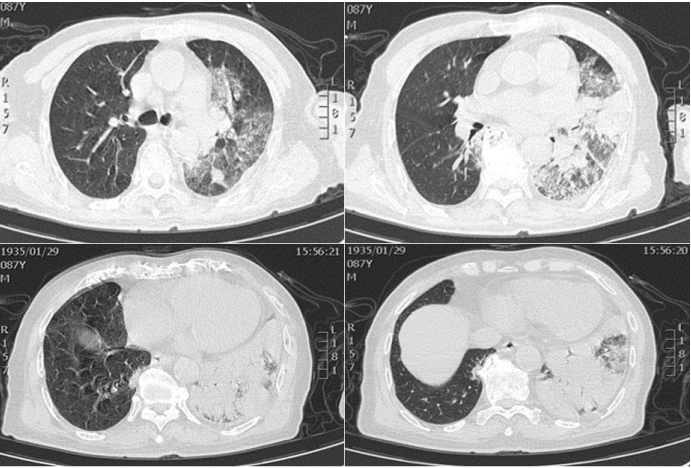

患者,男性,87岁,既往有高血压、房颤、脑梗死病史,因发热、气促、咳嗽,新冠病毒核酸阳性至方舱医院隔离,核酸转阴后居家隔离第3天突发意识障碍、跌倒后收住RICU。

查体:T 39℃,RR 28次/min,HR 110次/min,BP 80/50 mmHg,心律不齐,短绌脉,两肺呼吸音低,左肺可闻及管状呼吸音及少量细湿啰音。

血常规:WBC 14.11×109/L,NEU% 94.6%。

炎性标志物:CRP 170.53 mg/L,SAA 289 mg/L,IL-6 1648 pg/ml,PCT 4.97 ng/ml。

血生化:AST 419.6 U/L,ALT 156 U/L,TB 43.9 μmol/L,K+ 2.89 mmol/L,SCr 178.3 μmol/L。

凝血功能:D-Dimer 4.09 mg/L。

心肌酶谱:Pro-BNP 15090.0 ng/L,CK-MB 95.02 ng/ml,cTnI 0.159 ng/ml,肌红蛋白3000.0 ng/ml。

血气分析(FiO2 7 L/min):pH 7.417,PaO2 132.3 mmHg,PaCO2 32.0 mmHg,HCO3- 20.60 mmol/L,SaO99.20%, BLC 3.1 mmol/L。

ECG:房颤。

胸部CT:双肺轻度间质渗出,左肺斑片状渗出伴实变,左侧胸腔积液,左房、左室增大1

图片

图1  患者入院时胸部CT

入院诊断:脓毒性休克,多脏器功能不全(心、肝、肾),重症肺炎,心律失常:心房颤动。给予高流呼吸支持,抗感染、抗心律失常,液体复苏、脏器保护、营养支持治疗,行气管插管后床旁支气管镜防污染毛刷黏膜刷检+支气管肺泡灌洗术,待患者清醒、血流动力学稳定后拔管,序贯无创呼吸机及高流通气。

BALF细胞学检查:细胞计数120个,中性粒细胞38/50个,淋巴细胞2/50个。BALF G/GM试验阴性。床旁黏膜刷检+BALF离心沉淀涂片镜检:均找到革兰氏阳性球菌,抗酸杆菌及真菌阴性。NGS回报肺炎链球菌(序列数24);肺炎链球菌尿抗原阳性。

诊断:肺炎链球菌肺炎。抗感染方案调整为莫西沙星单药治疗,15天后患者临床症状明显好转,血常规、炎症指标恢复正常,心、肝、肾功能代偿,可予出院。出院1周后复查胸部CT可见病灶明显吸收2)

图2  患者出院1周后复查胸部CT